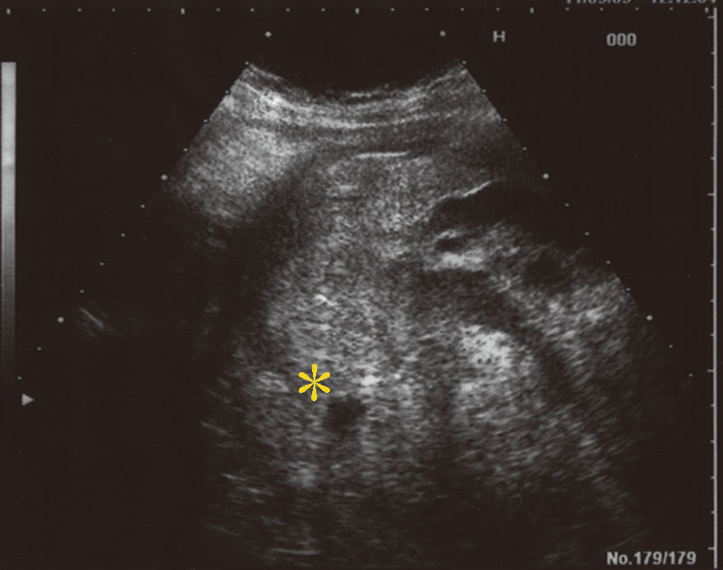

重症症例:子宮内胎児死亡からDICを来した症例

後壁から側壁に付着した胎盤が早期剝離を生じた症例の超音波断層法像である。血腫は黄色いアスタリスク(*)で示す。

出典

img

1: 著者提供